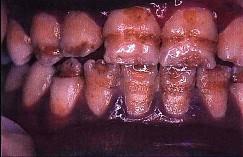

问题 釉质发育不全的临床表现是()

选项 A.釉质表面暗白不透明、无光泽 B.釉质表面缺损呈现蜂窝状 C.釉质表面呈深度不等的带状或窝状凹陷 D.缺损处无软化现象 E.以上均是

答案 E